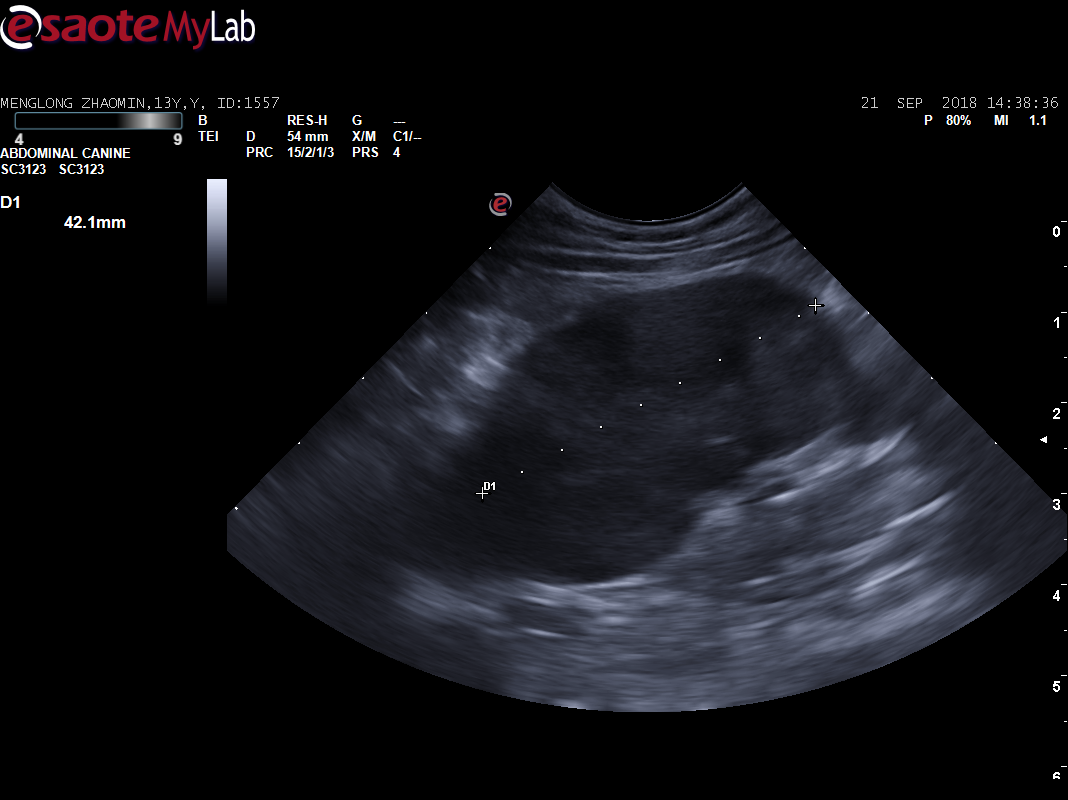

主人叙述2年前体检时,B超检查查出腹腔肿物(直径约6.1CM,场回声团块 ),主人当时选择保守治疗。每天吃完就吐,频繁的呕吐(3-4),导致梦龙体重急剧下降,主人十分担心。到我院初步诊断发现腹部触诊敏感,前腹部大肿物明显,为了准确评估梦龙的情况,医生对梦龙做了X光、生化和B超检查,进一步了解梦龙的身体情况。

B超显示:脾脏弥散性低回声(鉴别肥大细胞瘤、淋巴瘤、充血等),腹部肿物(鉴别淋巴瘤、肥大细胞瘤、肉瘤),肾脏(鉴别肾小球肾炎、慢性肾炎)。